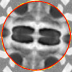

V-D Multiple Region Segmentation: Full Heart Segmentation

We now demonstrate our approach in performing challenging full heart segmentation: segmentation of the ventricles and epicardium all in one shot. Both the RV and epicardium are especially challenging as the contrast of the RV and background is subtle in comparison to the LV, and the myocardium wall near parts of the RV is very thin. We are not aware of another interactive method that is able to segment all structures, and so we compare to Medviso even though the method is not specifically tailored to the myocardium, but the method is generic and is able to propagate a segmentation. Further, Medviso does not segment multiple regions all at once and thus we perform separate segmentation of the LV, RV and epicardium. Since ground truth is not available for the outer wall of the myocardium in any standard dataset that we aware of, we show visual comparison.

Figure 10 shows the slice-wise results of our method and Medviso on a full 3D cardiac MRI sequence for a full cardiac cycle. Results indicate that our method is more accurate in capturing the shape of the ventricles and epicardium, and our method is especially more promising on the RV and epicardium. Figure 11 shows visualization of the results in 3D, and that our method more accurately resembles the structure of the heart.